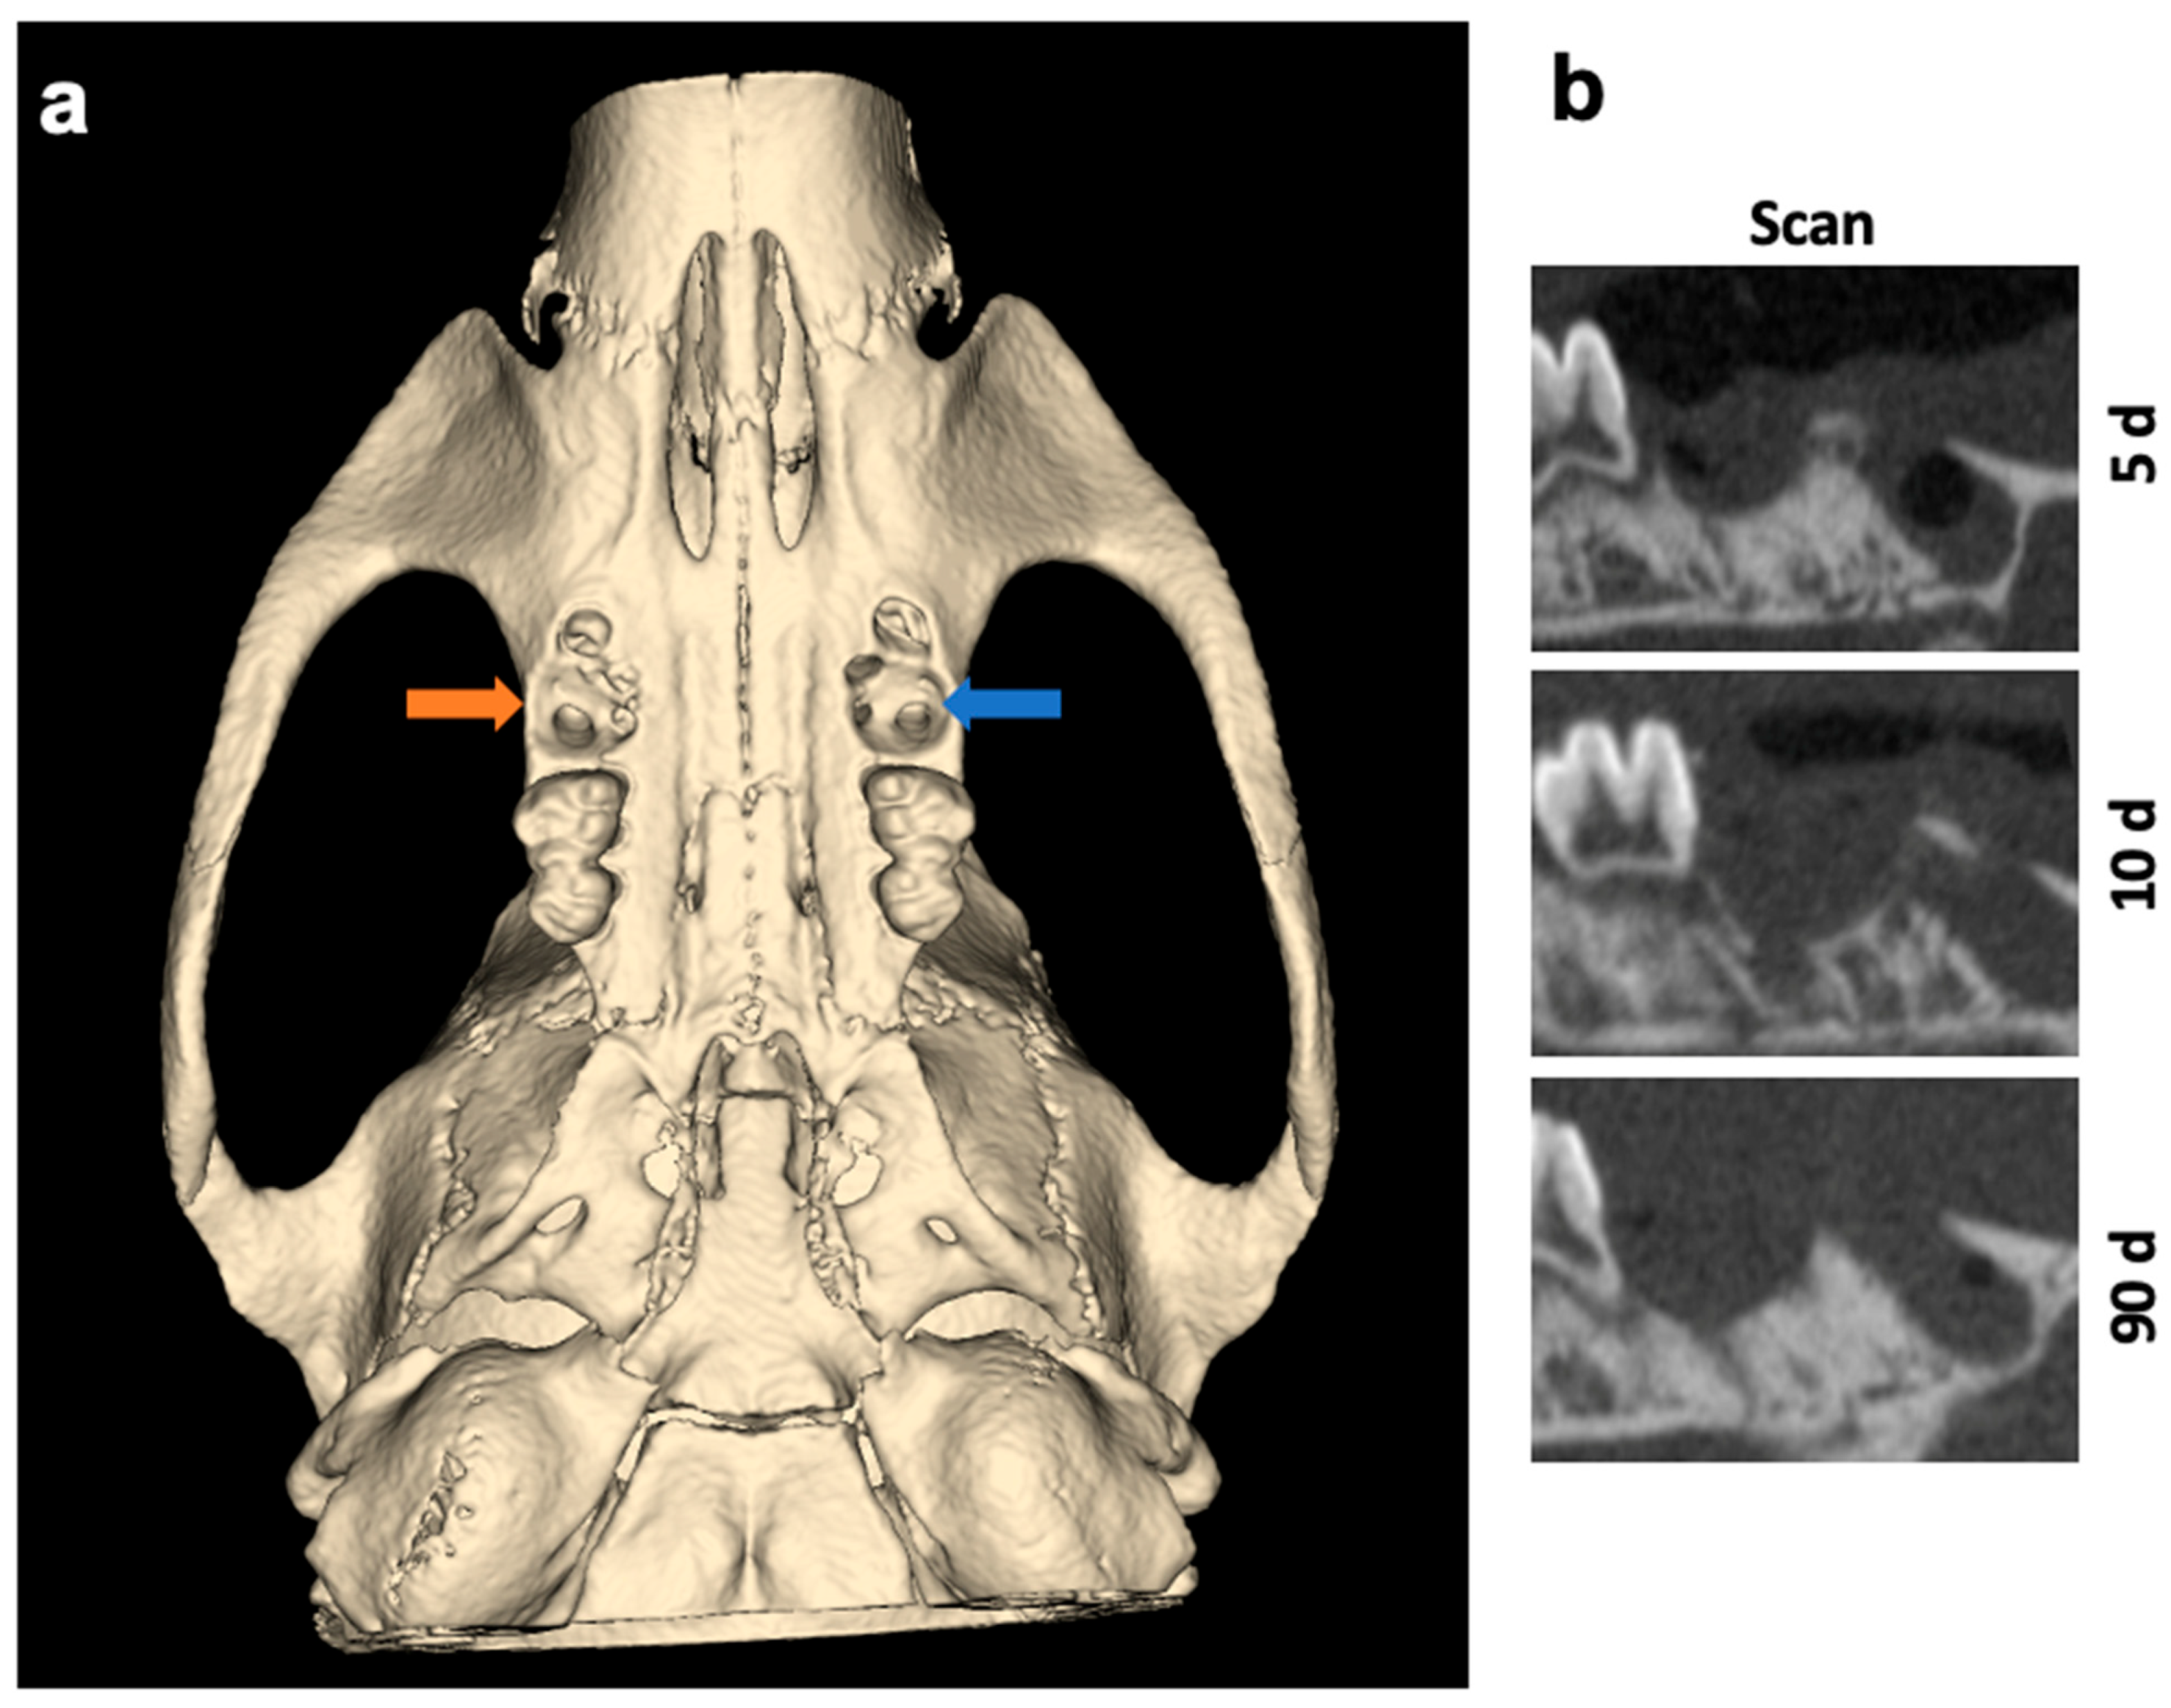

3. Discussion

4. Materials and Methods

4.4. Micro-Computed Tomography (µCT) Analysis